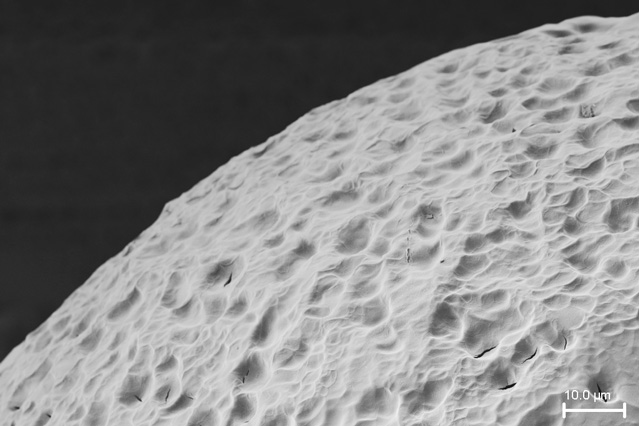

Hydrogel-based capsules could expand and reside

in the GI tract for days, slowly releasing medication